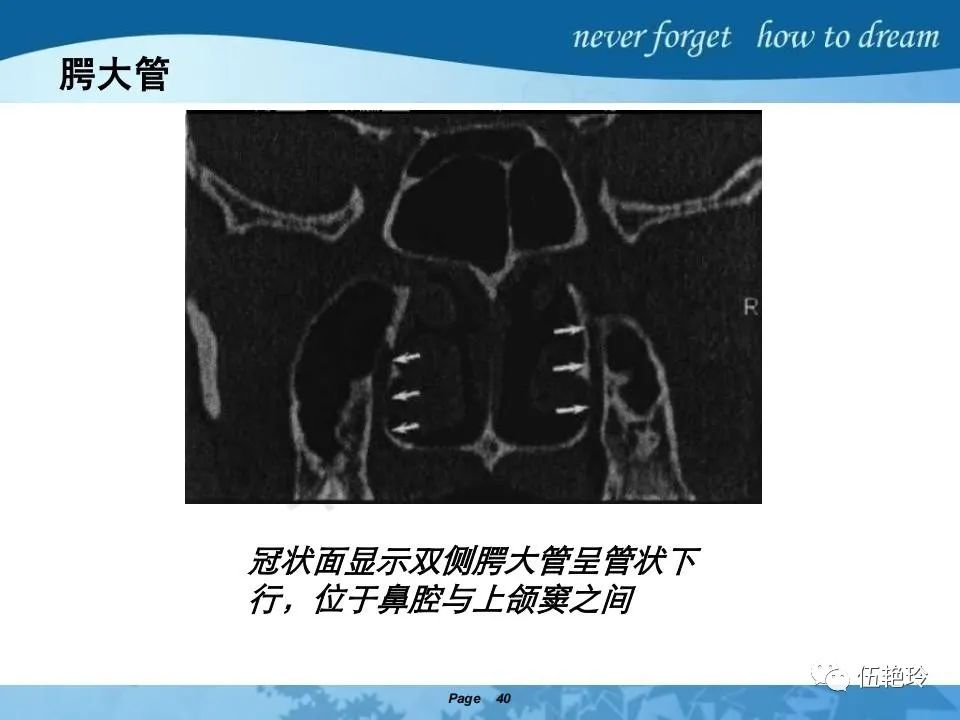

翼腭窝的解剖结构与鼻咽癌侵犯

2.2 鼻咽特有的解剖途径:鼻咽癌原发灶循序进展的总途径:鼻腔(47.8%)→翼腭窝(15.2%)→ 眶下裂(3.2%)→眶尖(1.2%)→海绵窦(0.6%)。

2.31 向上颅内:①鼻咽顶壁→破裂孔(岩尖、斜坡)→蝶窦、海绵窦;②鼻咽顶壁→蝶骨基底部→蝶窦、海绵窦;③鼻咽侧壁→茎突前间隙→蝶骨大翼(卵圆孔)→海绵窦;④鼻咽侧壁→茎突前间隙→翼腭窝→ 颞下窝;⑤鼻咽前壁→鼻腔→翼突、翼腭窝→眶下裂→眶尖→海绵窦;⑥鼻咽前壁→鼻腔→上颌窦、筛窦;